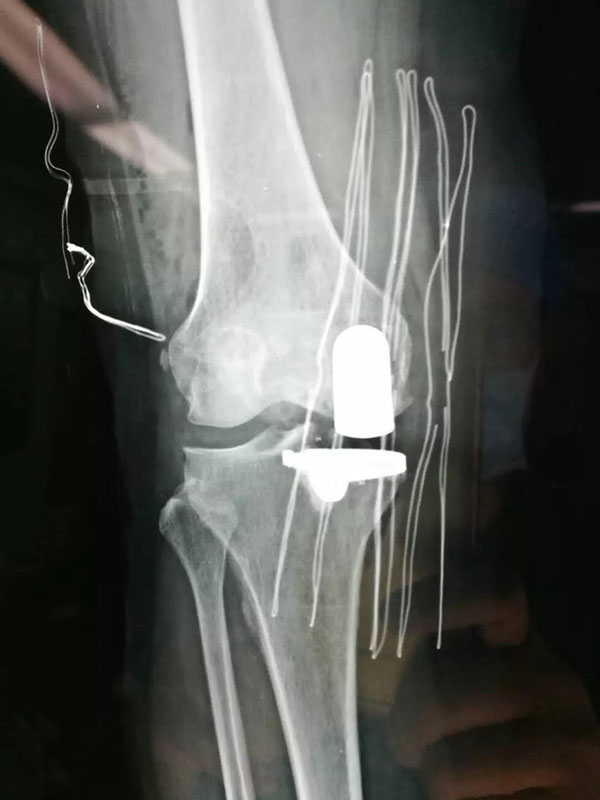

入院以后,骨一科主任邢亚萍、副主任吕红雨为患者进行了详细的术前检查及综合评估,并与骨科专家、院长殷晓东会诊商讨手术方案,最终决定采取微创手术实施关节置换,以解除患者的恐惧心里。魏阿姨入院的第三天,骨科专家殷晓东就带领骨一科副主任吕红雨、医师刘赛军为她实施了微创关节置换手术,手术没有像其他手术那样放置引流管、尿管等等各种管道,术后第二天,魏阿姨就能下床锻炼行走了。

北关院区骨一科病区副主任吕红雨介绍说,微创技术在关节置换的发展应用,使操作更加精确,更快速,对关节结构和周围软组织的损伤更加微小化,手术切口与原来相比,缩短一半以上。与传统的开放性手术相比优势明显,不仅保留了本体感觉,截骨少,创伤小,手术时间短,而且具有失血量少、恢复快及并发症少等优点,这种手术方法的关节置换材料使用寿命为10至20年,对于膝关节广泛严重磨损的中老年患者尤为适用。